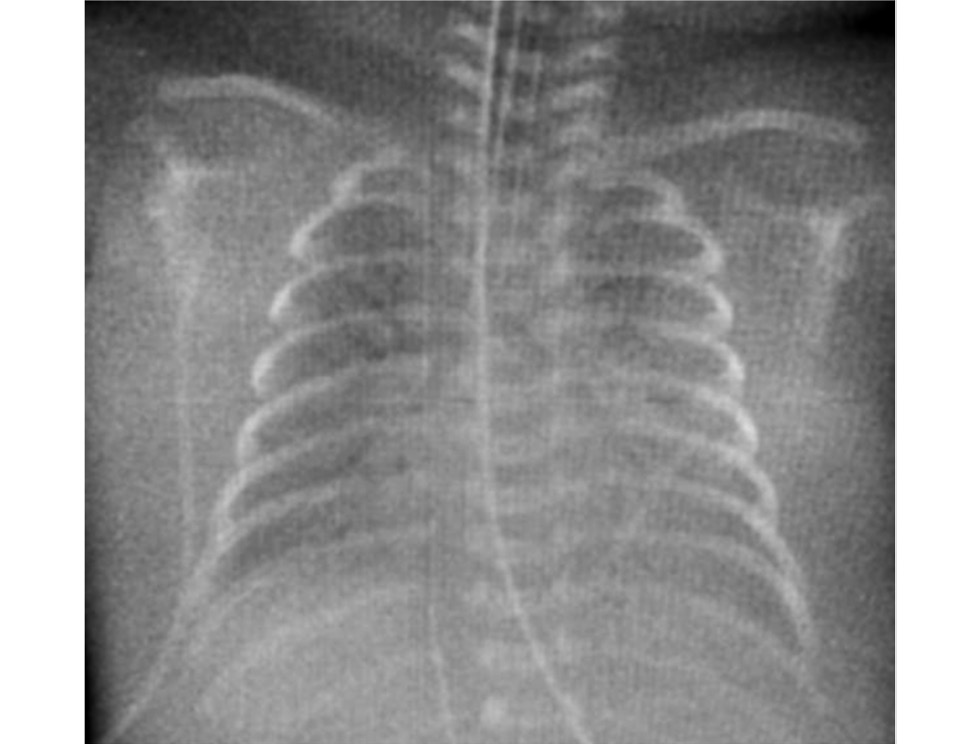

К 23 сут жизни отмечено прогрессирование ДН, отсутствие экскурсии грудной клетки справа, повышение кислородозависимости (фракция кислорода во вдыхаемой смеси до 65%). Диагностирован тотальный ателектаз правого лёгкого (ТАПЛ) с выраженным смещением органов средостения вправо (рис. 4).

Рис. 4. Рентгенограмма органов грудной полости на 23 сут жизни: тотальный ателектаз правого лёгкого.

Fig. 4. X-ray of the chest cavity on the 23rd day of life: total atelectasis of the right lung.